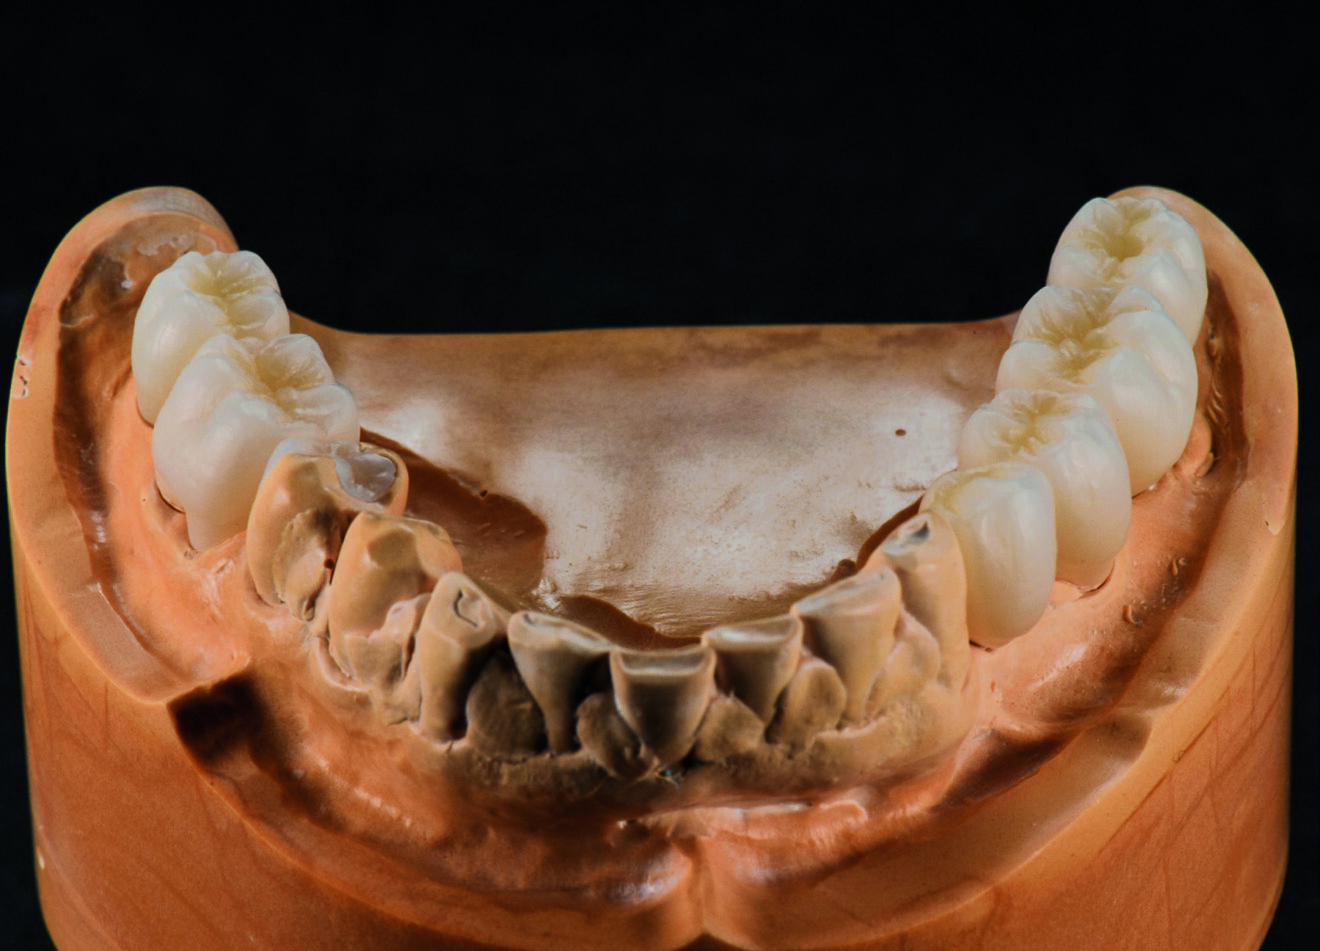

Une patiente de 50 ans atteinte d’une péri-implantite à un stade avancé, s’est présentée à notre laboratoire avec le souhait d’une restauration fonctionnelle et esthétique (Figs. 2a et b). Nous avons établi un plan de traitement qui consistait à traiter la péri-implantite, à poser de nouveaux implants et, finalement, à améliorer l’esthétique générale. Notre première étape a été de reconstruire complètement l’occlusion par une restauration en zircone Zolid FX Multilayer (Amann Girrbach), sauf pour les dents antérieures inférieures.

Une telle reconstruction requiert le plus grand nombre d’informations possible sur la patiente. Nous avons donc utilisé le système d’axiographie CADIAX (GAMMA Medizinischwissenschaftliche Fortbildungs-GmbH) pour obtenir les données sur les mouvements de l’articulation. Les données de transfert de l’arc facial, combinées à celles de l’articulateur Artex CR (Amann Girrbach) et du système CADIAX, sont nécessaires pour reproduire les mouvements mandibulaires avec l’articulateur virtuel (Figs. 3a et b).